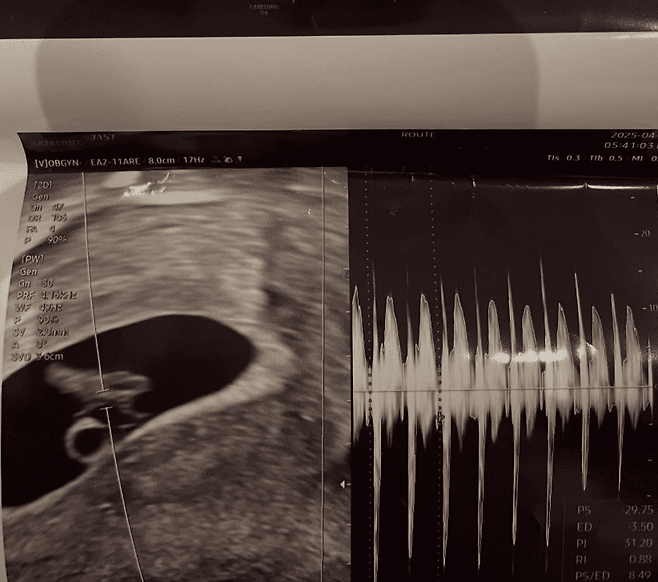

서민재는 SNS를 통해 A씨의 실명, 사진, 직장, 학교 등의 신상을 공개했고, 초음파 사진과 함께 "아빠 된 거 축하해"라는 글도 함께 게재했습니다. 이어 “연락을 시도했지만 일방적으로 차단당했다”며 클락션을 울리며 A씨의 집 앞을 찾아가는 등의 행동을 이어갔고, 결국 A씨 측은 스토킹, 감금, 폭행, 정보통신망법 위반(명예훼손) 등의 혐의로 서민재를 고소했습니다.